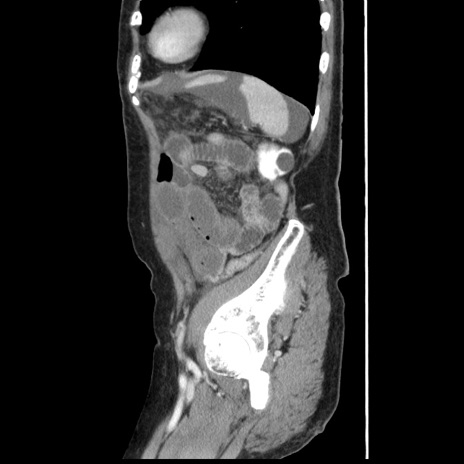

冠状断像